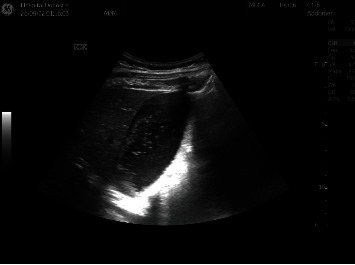

乳糜腹水是富含脂质的淋巴液渗入腹腔所致,在妊娠过程中极为罕见。这种病理现象表现为下腹或弥漫性腹痛的病例不胜枚举,而我们的报告则强调了一种独特的表现形式,即一名怀孕 35 周的孕妇出现剧烈上腹痛,与妊娠高血压或其他胃肠道疾病无关。排除了主要的产科急性病症,也没有胎儿窘迫的证据。由于疼痛无法控制,病因不明,且比绍普评分不理想,医生紧急实施了剖腹产手术。手术中观察到大量乳白色液体,随后证实为乳糜液。新生儿和母亲术后均恢复良好。虽然乳糜泻通常是一种良性病症,但医护人员仍有必要了解这种病症,以便及时提供医疗护理和适当的治疗。

Chylous ascites results from the leakage of lymph rich in lipids into the peritoneal cavity and represents an exceedingly rare event in the course of pregnancy. While there are numerous documented instances of this pathology manifesting with hypogastric or diffuse abdominal pain, our report highlights a unique presentation involving a 35-week pregnant woman experiencing severe epigastric pain unrelated to pregnancy-induced hypertension or other gastrointestinal disorders. Major acute obstetric pathologies were ruled out, and there was no evidence of fetal distress. Due to uncontrolled pain with an unidentified etiology and an unfavorable Bishop score, an urgent cesarean section was performed. A copious amount of milky fluid was observed during the surgery, subsequently confirmed as chylous in nature. Both the newborn and the mother had positive outcomes postsurgery. Although it is usually a benign condition, it is important for healthcare professionals to be aware of this entity in order to provide timely medical care and administer appropriate treatment.